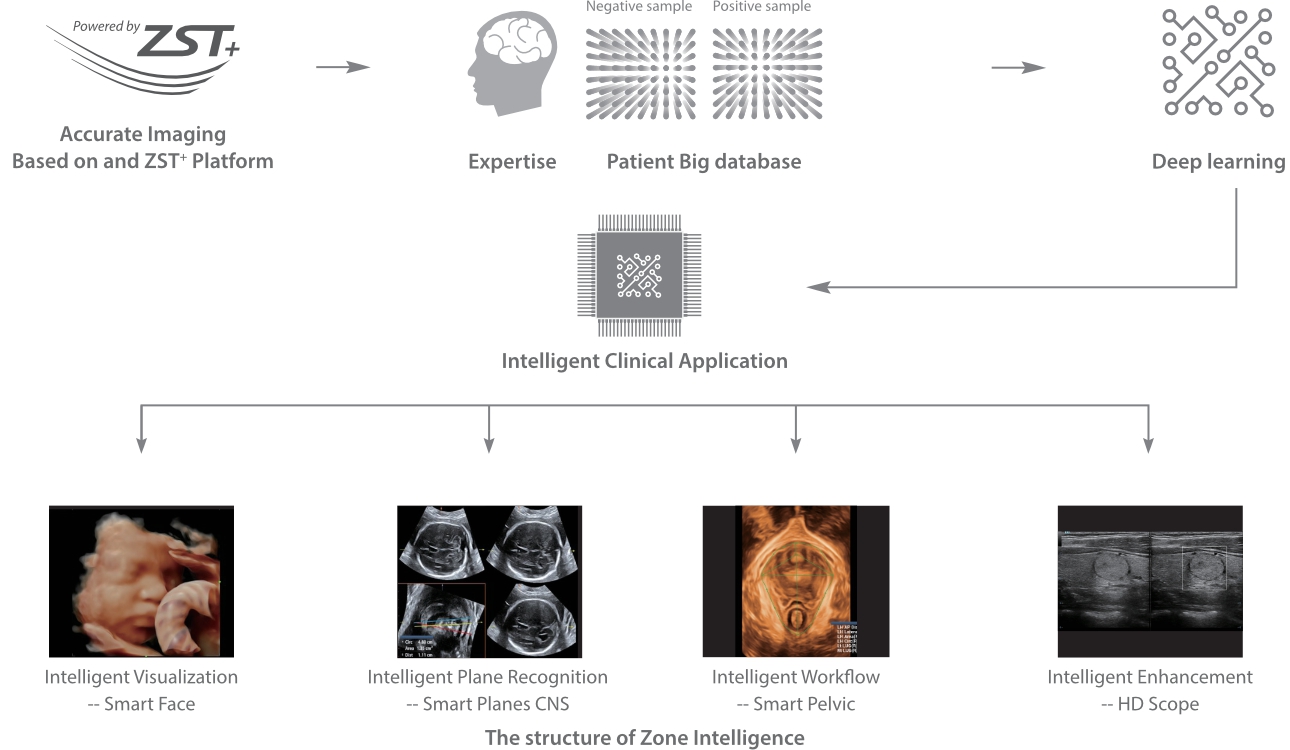

Desde su creaciÃģn, Mindray no ha dejado de explorar nuevas maneras de mejorar la fiabilidad del diagnÃģstico. Gracias a ZONE Sonography?, la tecnologÃa mÃĄs revolucionaria, la nueva plataforma ZST+ del Resona 7 eleva la calidad de imagen de ultrasonido mediante la adquisiciÃģn de zonas y el procesamiento de datos de canal.

AdemÃĄs de una calidad superior de la imagen, el Resona 7 tambiÃĐn mejora las capacidades de investigaciÃģn clÃnica gracias al revolucionario V Flow para la evaluaciÃģn hemodinÃĄmica vascular y la adquisiciÃģn de planos mÃĄs inteligente a partir de un conjunto de datos 3D para el diagnÃģstico CNS fetal. Combinando el funcionamiento multitÃĄctil mÃĄs intuitivo basado en gestos y todas las funciones clÃnicas esenciales, el Resona 7 estÃĄ realmente encabezando nuevas ondas en la innovaciÃģn del campo del ultrasonido.